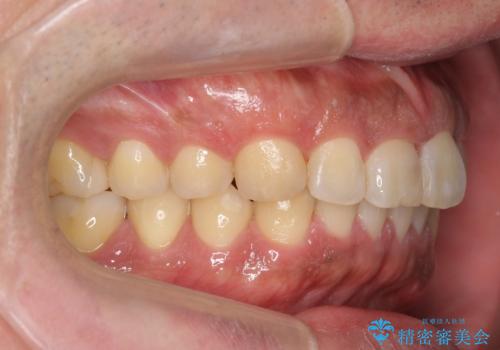

前歯のねじれを 1年かけずに矯正 インビザライン

- 前歯のねじれを主訴に来院。

インビザラインで治療しました。

前歯のねじれをセラミックで治そうとすると、抜髄といって、神経の治療が必要になる上、歯の幅も制限が出て理想的にはなりません。

保定の必要がありますが、天然歯を並べる矯正治療では、治療後の心配事が非常に少なく、保存的な処置となります。